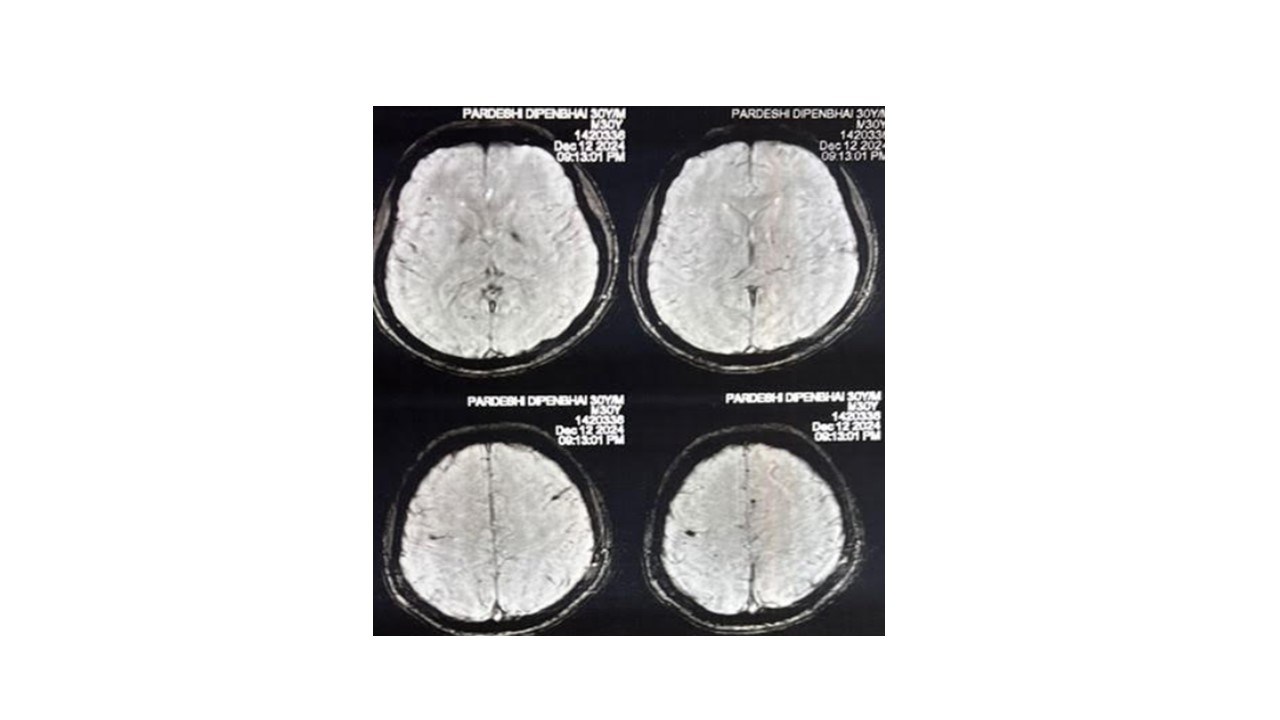

Results: On admission, his blood glucose was 420mg/dl, HbA1c was 12.2% (Normal <6%), serum osmolality of 279mOsm/Lit (Normal 275-295), and INR of 1.35. Electrolytes, Renal function and Liver function test was normal. EEG was normal. MRI Brain shows chronic microbleeds in bilateral cerebral and cerebellar hemisphere (Fig-1). The dystonic tremors and neck dystonia were completely controlled after achieving target range glycemic control with insulin, and was discharged on insulin and oral anticoagulant treatment.

SWI-chronic microbleeds in B/L cerebral hemisphere